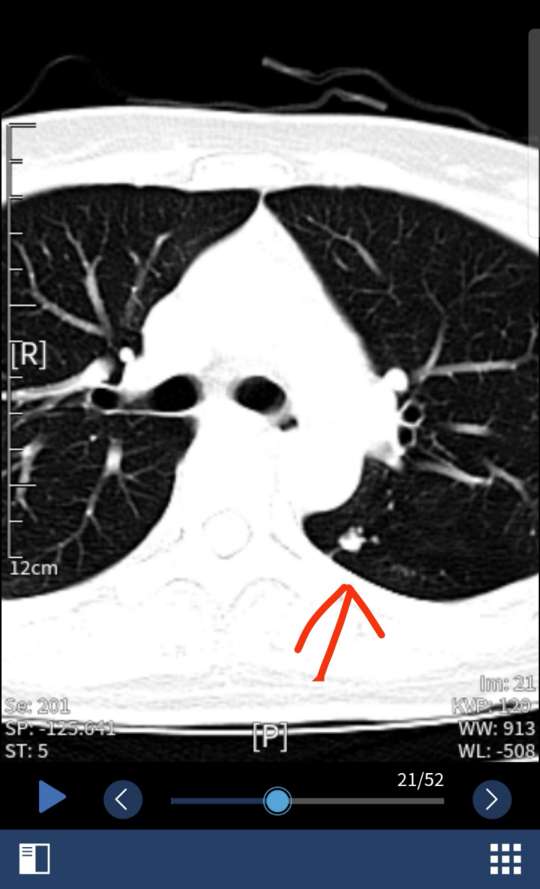

乳腺癌 肺小结节可能转移

图片尺寸540x889